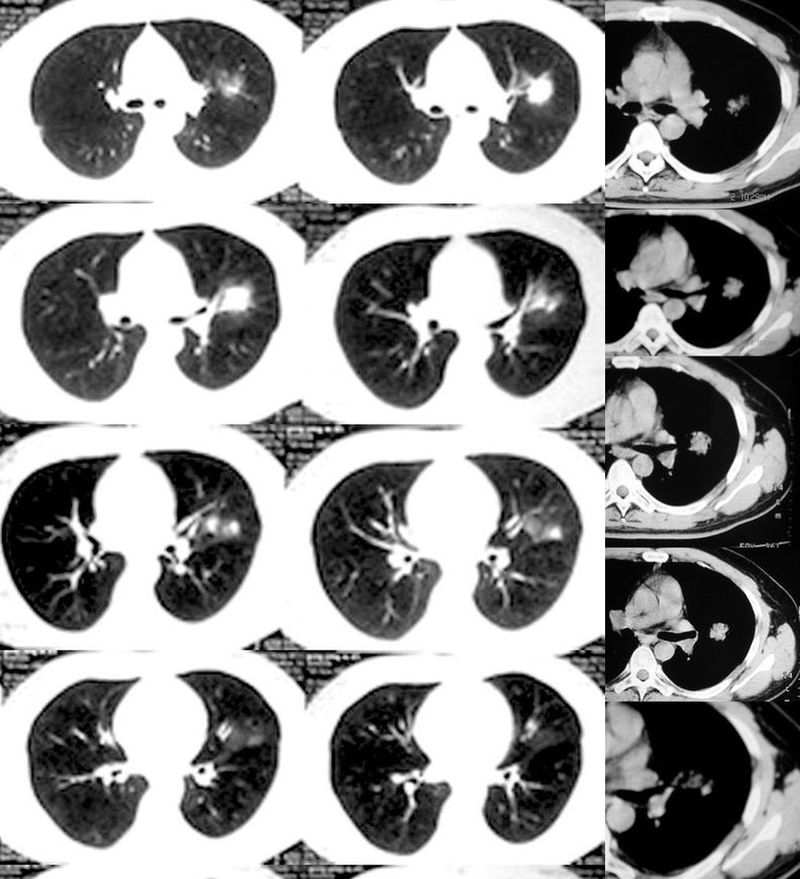

肺癌--腺癌

ct1746 pingfanjun提供 结果右上肺腺癌

76岁;咳嗽、咯血、气短、呼吸困难一年余

ct1847 九目段提供

m/71y,咳嗽咳痰,痰中带血,低热。

ct1962:mzjctmr提供 肺穿病理结果为腺癌

女性,43岁,刺激性干咳4个月,血象血沉正常,无发热

ct2060 liuzhiguang 提供 病理中分化型腺癌

ct2240 mzjctmr提供 病理结果为高分化腺癌并支气管淋巴转移

女性,60岁,夜间发热一周余就诊。体温38度,血沉35mm/h

ct1649:guzhongliangddd提供 胸部腺癌

ct2209:guzhongliangddd提供 病理结果腺癌

男,42。体检偶然发现。纵隔肺门无增大淋巴结

ct2182 丁海岸提供 穿刺,结果为肺鳞腺癌http://www.radida.com/radinet/read.php?tid=8348

ct2607 jiajie提供 手术肺叶切除,病灶大小约6x5cm,边缘有小溃口。

病例结果:未分化癌(巨细胞癌?),肺门两枚淋巴结查到癌细胞。

男性,37岁,咳嗽、胸闷,无咳血,无明显发热病史。体形消瘦。